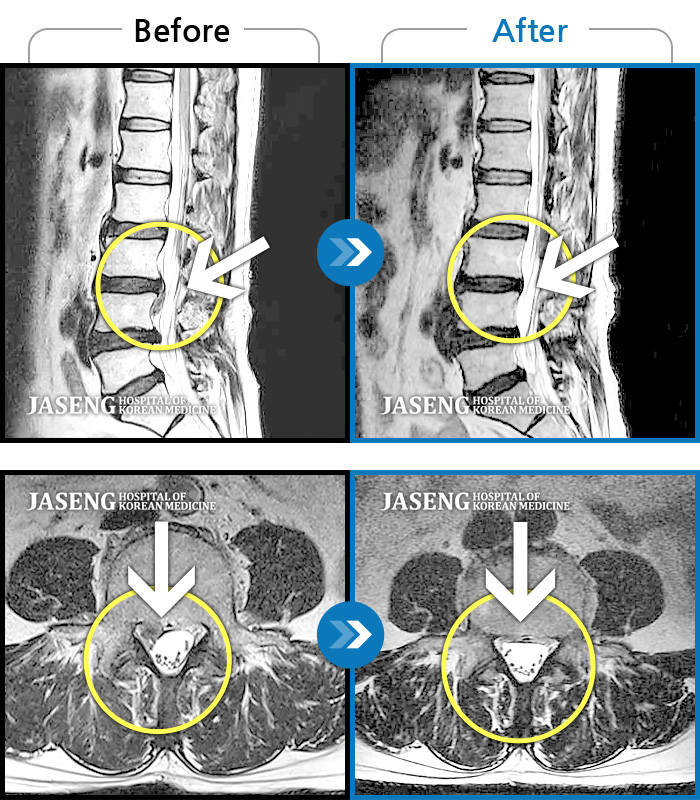

MRI ġ

119 MRI ũ ʸ Ȯϼ.

㸮 ٸ Ǵ

ǿ

Ȼ

ȯ

㸮ũ

μ

¥

2020.04.24

ȸ

933

[Ȼ] 19.08.28~20.04.22

ȯںп Ǹ ǿ ԿǾ, ο ġ ۿ Ƿ ġḦ Ͻñ ٶϴ.